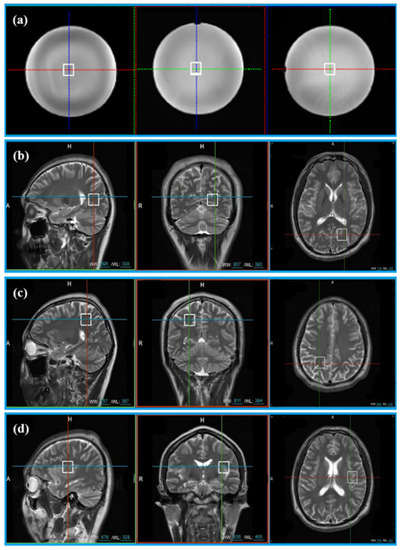

The General Electric golden standard phantom sphere was used for phantom experiments. Voxel locations of the sphere are shown in Figure 2a. The simulated correlation noise between coils was added to phantom experiments with different noise levels [13,16,17]. The simulated noise of each repeated sampling was independently generated according to the in vivo spectrum as follows.

Figure 2.

The location of voxels acquired from phantom and 11 healthy volunteers. (a) Voxel location of the phantom; (b) voxel LA, (c) voxel LB, and (d) voxel LC are the voxel locations of 11 healthy subjects.

In vivo data were acquired from 11 healthy volunteers with the approval of the Institutional Review Board of Shanghai Jiao Tong University. Informed consent was obtained from all volunteers before the study began. Three healthy volunteers were scanned at three different voxel locations (Location A (LA), Location B (LB), and Location C (LC)) in Figure 2b–d. Five healthy subjects were scanned at the LA only and other three healthy subjects were scanned at LB and LC. Finally, totally, 20 MRS were acquired for validation (see Table 1 for details).